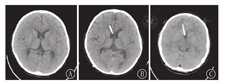

患儿均在急诊就诊期间行头颅CT检查,多数患儿急诊就诊时头痛剧烈难以耐受MRI,故仅个别患儿(例10)急诊完善头颅MRI检查。SVS发生时,头颅CT示脑室形态呈裂隙样、分流管位置贴壁。患儿脑室-腹腔分流术前、术后以及发生SVS时的头颅影像学表现见图1,图2。

本研究10例患儿诊断时头颅影像学均示脑室呈裂隙样,即SVS独特的影像学特征。通常脑脊液长期过度引流导致脑室缩小,急性静脉梗阻迅速进展时,脑室并不会扩大;若静脉窦压力高于分流泵压力时,分流泵开放、脑脊液引流,脑室进一步缩小,最终呈裂隙样脑室。可采用额枕角比率(FOHR)评估裂隙样脑室,即轴位侧脑室层面额角与枕角最大宽度的平均值/双顶径。FOHR正常值约为0.37,与年龄无关;FOHR≤0.2时,考虑裂隙样脑室[7]。值得注意的是,并非所有脑室呈裂隙样的患儿均为SVS,SVS诊断须具备相应临床症状。研究显示,分流术后超过50%的患儿可能会出现裂隙样脑室的征象,但仅6%~22%最终为SVS[15,16]。